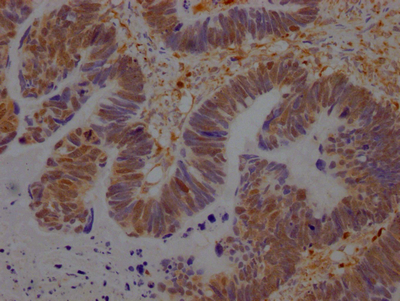

• IHC image of CSB-RA981267A0HU diluted at 1:100 and staining in paraffin-embedded human ovarian cancer performed on a Leica BondTM system. After dewaxing and hydration, antigen retrieval was mediated by high pressure in a citrate buffer (pH 6.0). Section was blocked with 10% normal goat serum 30min at RT. Then primary antibody (1% BSA) was incubated at 4℃ overnight. The primary is detected by a Goat anti-rabbit IgG polymer labeled by HRP and visualized using 0.05% DAB.